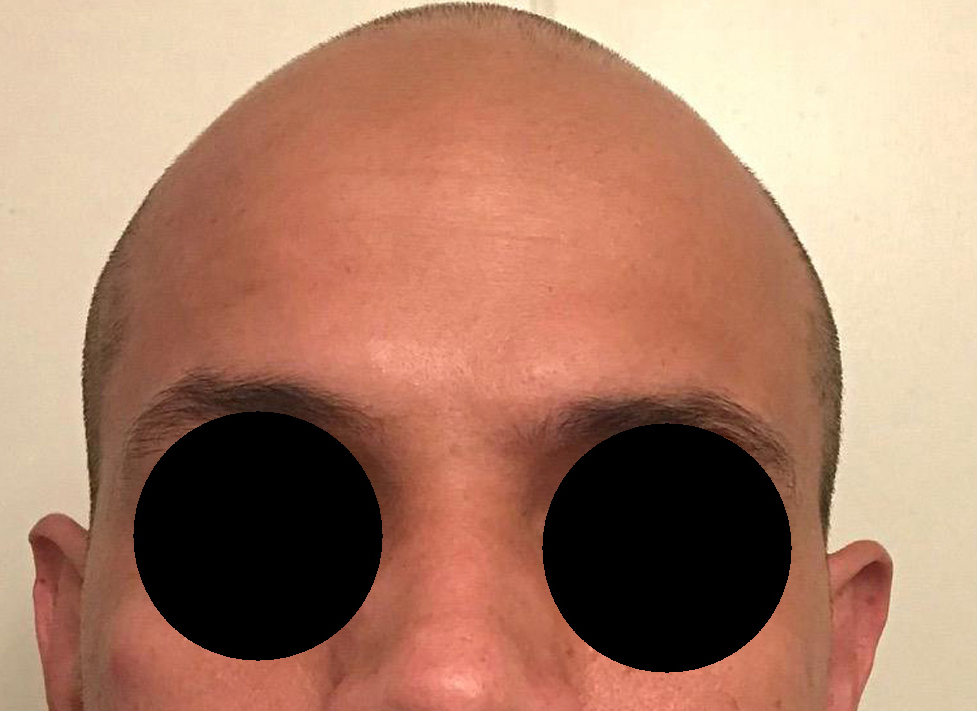

Patient 100

Desire for reshaping of an asymmetric flat back of the head in a shaved head male.

A combined back of the head reshaping procedure was done with a custom skull implant, sagittal ridge reduction and a right temporal muscle reduction.

Desire for reshaping of an asymmetric flat back of the head in a shaved head male.

A combined back of the head reshaping procedure was done with a custom skull implant, sagittal ridge reduction and a right temporal muscle reduction.